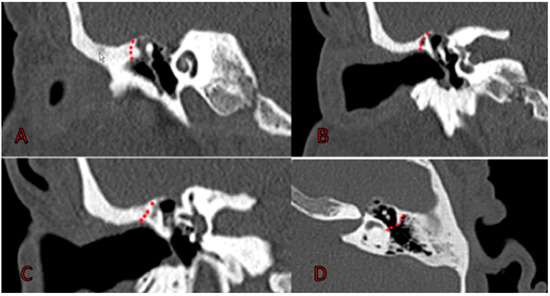

- Atticotomy (M2a). Superior wall of EAC is drilled with two hands and microscopic control, exposing entire tegmen tympani. Once attic is completely exposed (Figure 4), cholesteatoma is removed. If it invades medial region of attic, it is necessary to remove incus and head of malleus. At this point, we use an otoendoscope at 0 and 30° degrees to thoroughly check the epitympanum, sinus tympani, and antrum;